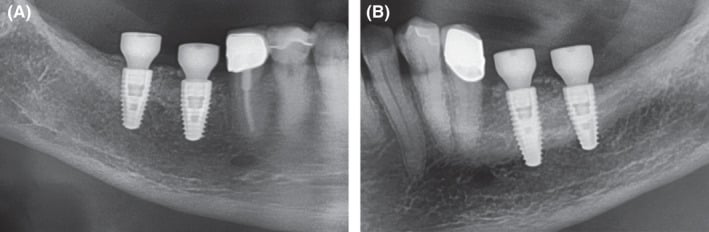

Figure 7.

Extracts from postoperative OPG after implantation and GBR in the third and fourth quadrant. A, fourth quadrant. B, third quadrant

Figure 10.

Extracts from postoperative OPG: Gingival former in the third and fourth quadrants in situ. A, Allogeneic site showing good integration of the implants and no loss of crestal bone. Relining layer of DBBM particles in situ. B, Same situation on the autologous site showing similar results compared to the allogeneic site

Figure 12.

Extracts from OPG: Radiological situation after prosthetic treatment. A, Allogeneic site with good integration of the implants and no crestal bone loss and well‐integrated relining layer. B, Autologous site showing good integration, no bone loss and well‐integrated relining layer on the autologous site